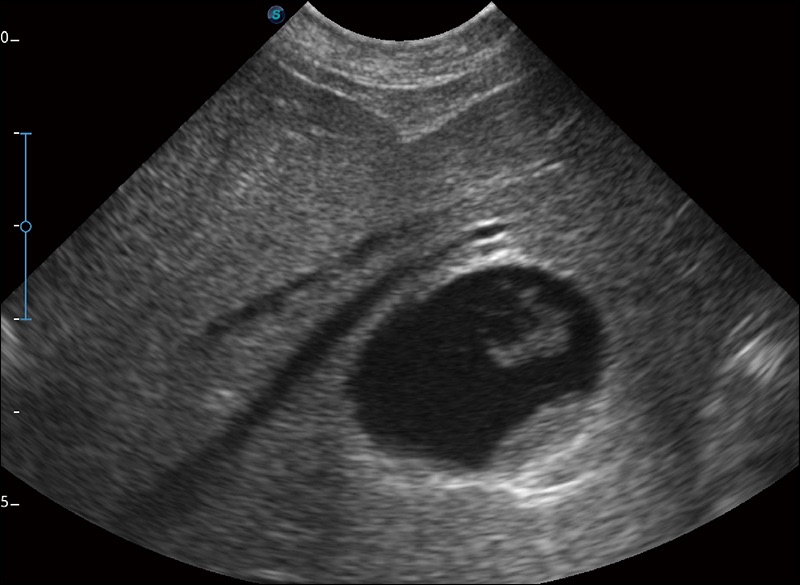

α1卓越的图像质量和便捷的工作流程,使每位宠物医生都能轻松扫查。其全面的兽用应用功能和紧凑型的结构设计,可以满足动物检查的多种需要。专业的预设检查模式和多领域测量软件包有助于为不同类型的动物提供检查, 让宠物医生能够出色的完成工作。

为心脏功能评估提供更多诊断信息